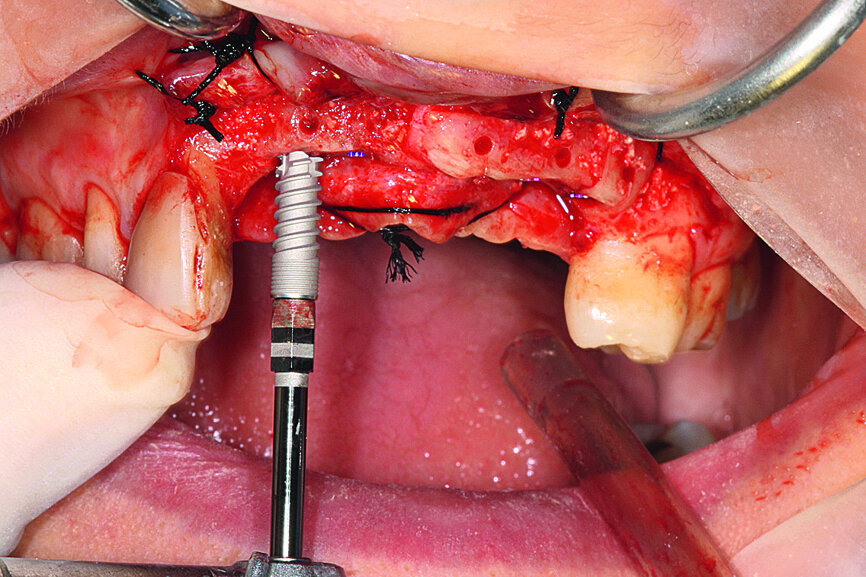

Implant placement

Local anaesthesia was administered and the bone site reopened. The site showed correct integration of the grafts, a notable increase in cortical bone and excellent vascularity throughout the site (Fig. 13). The sterilised surgical drilling guide was tested and showed that drilling would in fact be at the centre of the reconstructed bone ridge (Fig. 14).

After removal of the screws stabilising the grafts, the guide was placed and drilling (using physiological saline solution) completed. Five Aadva (GC Tech.Europe) self-tapping Grade 5 titanium microstructure implants were inserted by slow drilling (Fig. 15). Aspiration with physiological saline solution was not used at this time so that the first contact with the titanium oxide would be the patient’s blood, thus promoting the implants’ osseointegration. This specific implantation technique was validated by Brun et al. [6] All of the implants were equipped with threaded cover screws and the surrounding tissue was sutured (Fig. 16).